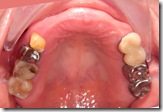

患者A先生

上顎 正面 下顎

患者B小姐

以上兩位患者口內狀況非常複雜,要制定一個好的治療計畫,

不只要考慮到患者的牙齒條件,

還要顧及患者意願、時間、金錢、評估可獲得的結果等等。

所以像這類型的Case 醫師通常在初步的溝通後會先做出一兩個不同的治療計畫,

再和患者解釋,了解患者接受程度。